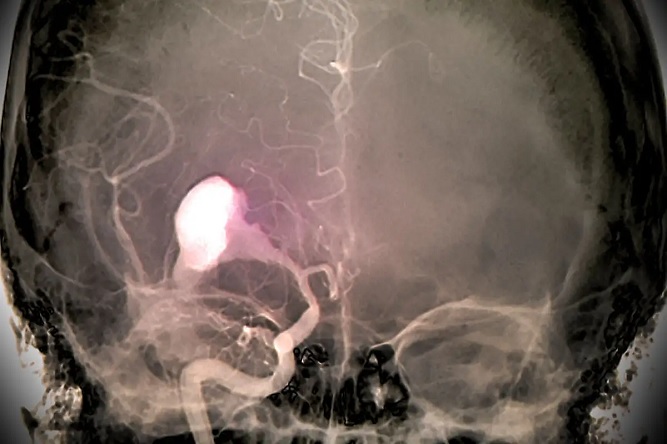

یکی از مواردی که به تازگی دانشمندان در آن رو به استفاده از هوش مصنوعی آوردهاند در زمینه شناسایی خونریزی مغزی و تشخیص سریع بیماران در حین تصادفات است.

طی تحقیقی جدید که در همکاری بین دانشمندان دانشگاه UC Berkeley و UCSF صورت گرفته این دانشمندان الگوریتم هوش مصنوعی را توسعه دادهاند که ادعا میشود میتواند صحت تشخیصی بهتر از دو تا چهار متخصص رادیولوژیست داشته باشد.

این سیستم برای دریافت دادههای آموزش خود اطلاعات جمعآوری شده از بیش از 4396 نمونه CT Scan که از قبل مورد واکاوی دادهای قرار گرفتهاند را مورد پردازش قرار داده و سپس از آنها الگوی خود برای شناسایی خونریزی مغزی را استخراج میکند.

در این حالت هنگامی که تصویر CT Scan مغزی فرد به الگوریتم داده میشود با توجه به شناسایی نقاط آسیب دیده در سطح پیکسل، سعی میشود تا احتمال وقوع خونریزی مغزی را مورد کاوش قرار داده و در صورتی که به سطحی از اطمینان رسیدیم، اعلام خونریزی در آن ناحیه مغزی صورت میگیرد.